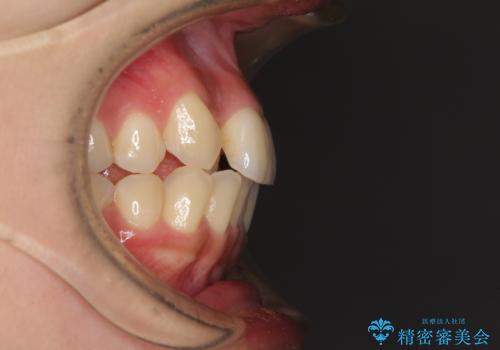

上顎右側犬歯が八重歯になっており、それによって奥歯が前方に移動しているため、右側の咬み合わせの改善が必要と判断されました。

マウスピース矯正では改善に時間がかかる、あるいは改善しきれない可能性があることを伝えたところ、短期間で確実に治療ができるワイヤー矯正を選択されました。